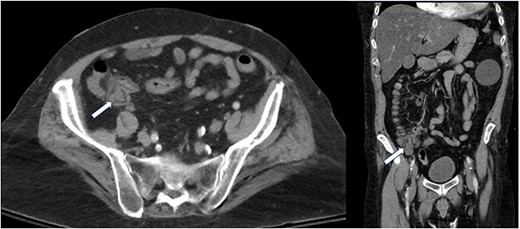

A computed tomography of the abdomen and pelvis (CT A/P) revealed a lobulated 2.4 × 2 cm mass at the cecal base without ascites or obvious metastatic disease (Fig. 1).